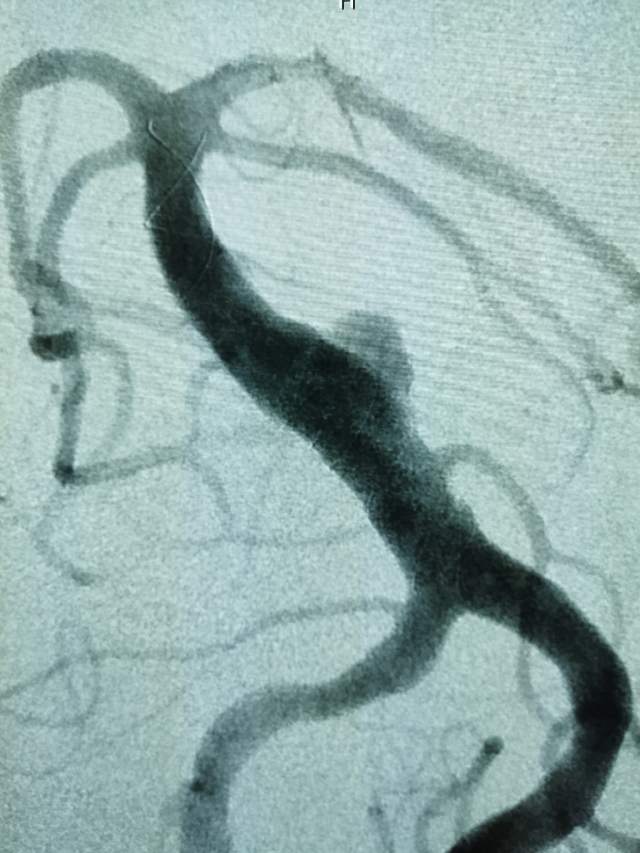

患者男性,34岁,年前自新疆坐车48小时来到我院,诊断:椎基底动脉冗长扩张症,出现脑干压迫症状、后组颅神经症状、部分中组颅神经症状、小脑症状、颅内压增高(220mmHg),症状进行性加重,最大径15mm,血管外面存在血栓造影只能窥见部分,短短两周,病变形态出现明显变化,局部出现明显瘤样凸起(图2-3),手术方案只能临时改变,植入血流导向装置,术后看病人语言、四肢活动均正常,围手术期仍然是一个艰巨的过程,充满了不确定因素,希望患者能安全度过围手术期,早日康复,重返工作岗位~~~